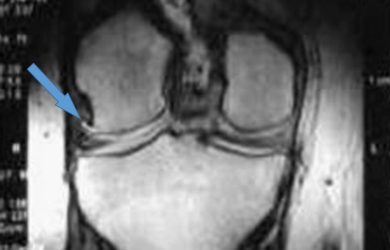

Хвороба Кеніга (розсікаючий остеохондрит колінного суглоба) – досить рідкісне захворювання, при якому розвивається обмежений остеонекроз ділянки субхондральної кістки,